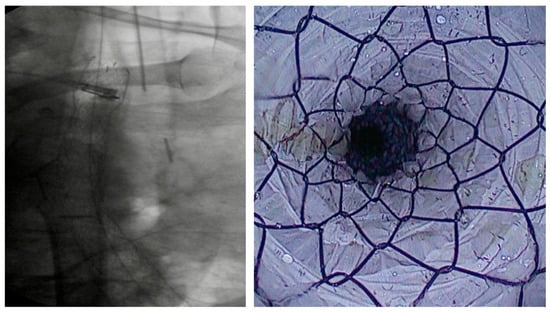

4.1.2. LAMS

Indication and Mechanism of Action

- Direct technique: puncture of the jejunal loop with a 19G needle and contrast injection to confirm position [126].

- Device-assisted EUS-GE: balloon or enteroscope passed across the stenosis to aid EUS visualization and targeting [127].

- Wireless Endoscopic Simplified Technique (WEST): described by Bronswijk et al. in 2020 and currently the most widely used technique [128], this approach involves jejunal distension via a nasoenteric tube with saline and dye, followed by “free-hand” single-step LAMS deployment under EUS guidance [128].

Efficacy and Adverse Events

- Type 1 (63.1%): distal flange in the peritoneum, proximal in the stomach, without enterotomy—managed with LAMS removal and OTSC placement.

- Type 2 (30.4%): distal flange in the peritoneum, proximal in the stomach, with confirmed enterotomy—managed with repeat LAMS or LAMS-in-LAMS bridging.

- Type 3 (2.2%): distal flange in the small bowel, proximal in the peritoneum—managed surgically.

- Type 4 (4.3%): distal flange in the colon, proximal in the stomach—managed conservatively or surgically after tract maturation.